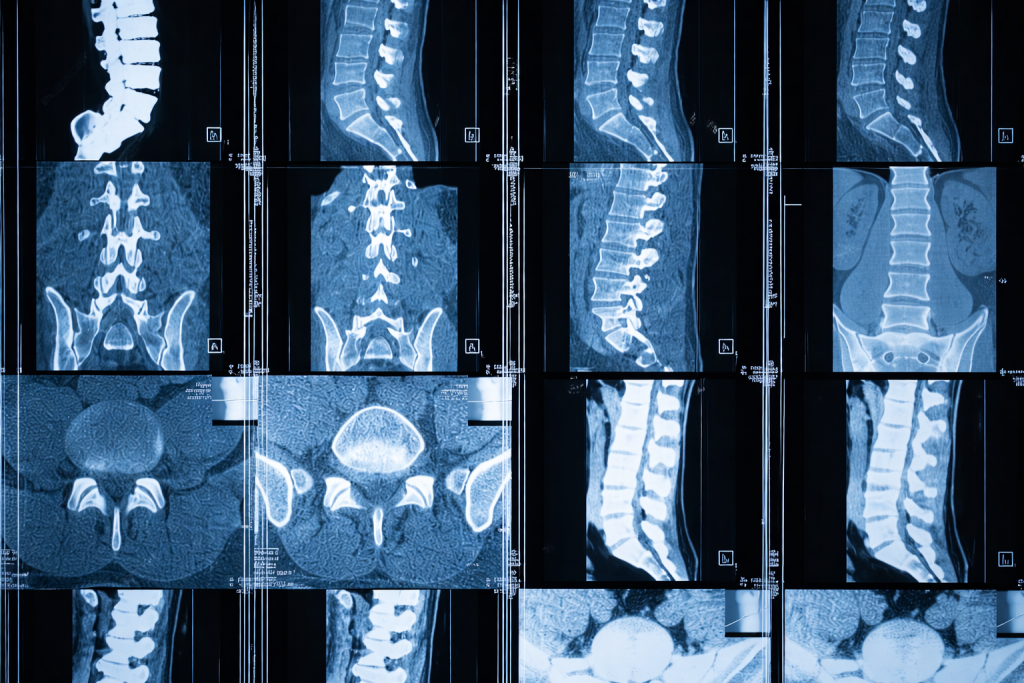

МРТ в данном случае становится незаменимым диагностическим инструментом. Исследование позволяет комплексно оценить состояние позвоночника, крестцово-подвздошных суставов, мягких тканей ягодичной области и самого седалищного нерва — и найти тот источник боли, который не виден на рентгеновском снимке и не определяется при обычном осмотре.

МРТ пояснично-крестцового отдела позвоночника — первый шаг при большинстве случаев боли в ягодице с иррадиацией. Исследование позволяет оценить состояние межпозвонковых дисков (наличие протрузий и грыж, их размер, направление и степень компрессии корешков), позвоночного канала и его просвета, дугоотростчатых (фасеточных) суставов, жёлтой связки, тел позвонков и костного мозга. На МРТ хорошо видны грыжи дисков, стенозы, спондилолистез, воспалительные и опухолевые изменения позвонков.

При грыже межпозвонкового диска МРТ показывает выпячивание дискового материала за пределы тела позвонка — протрузию (до 3 мм) или грыжу (более 3 мм). Оценивается направление выпячивания (заднее, заднебоковое, фораминальное), степень компрессии дурального мешка и нервных корешков, наличие секвестра (фрагмента диска, отделившегося от основной части). Важен также сигнал от самого диска: снижение интенсивности в режиме T2 указывает на его дегидратацию и дегенерацию.

При стенозе позвоночного канала МРТ наглядно показывает уменьшение площади поперечного сечения канала, компрессию дурального мешка, гипертрофию жёлтых связок и фасеточных суставов, а также поясничный спондилолистез — смещение одного позвонка относительно другого. При выраженном стенозе на T2-взвешенных изображениях дуральный мешок может выглядеть как «пустой» — без нормальной картины ликвора вокруг корешков.

КТ позвоночника превосходит МРТ в визуализации костных структур — остеофитов, фораминальных стенозов костного происхождения, переломов. Однако КТ значительно уступает МРТ в оценке состояния дисков, нервных корешков, связок и мягких тканей, к тому же связана с лучевой нагрузкой, что ограничивает её применение.